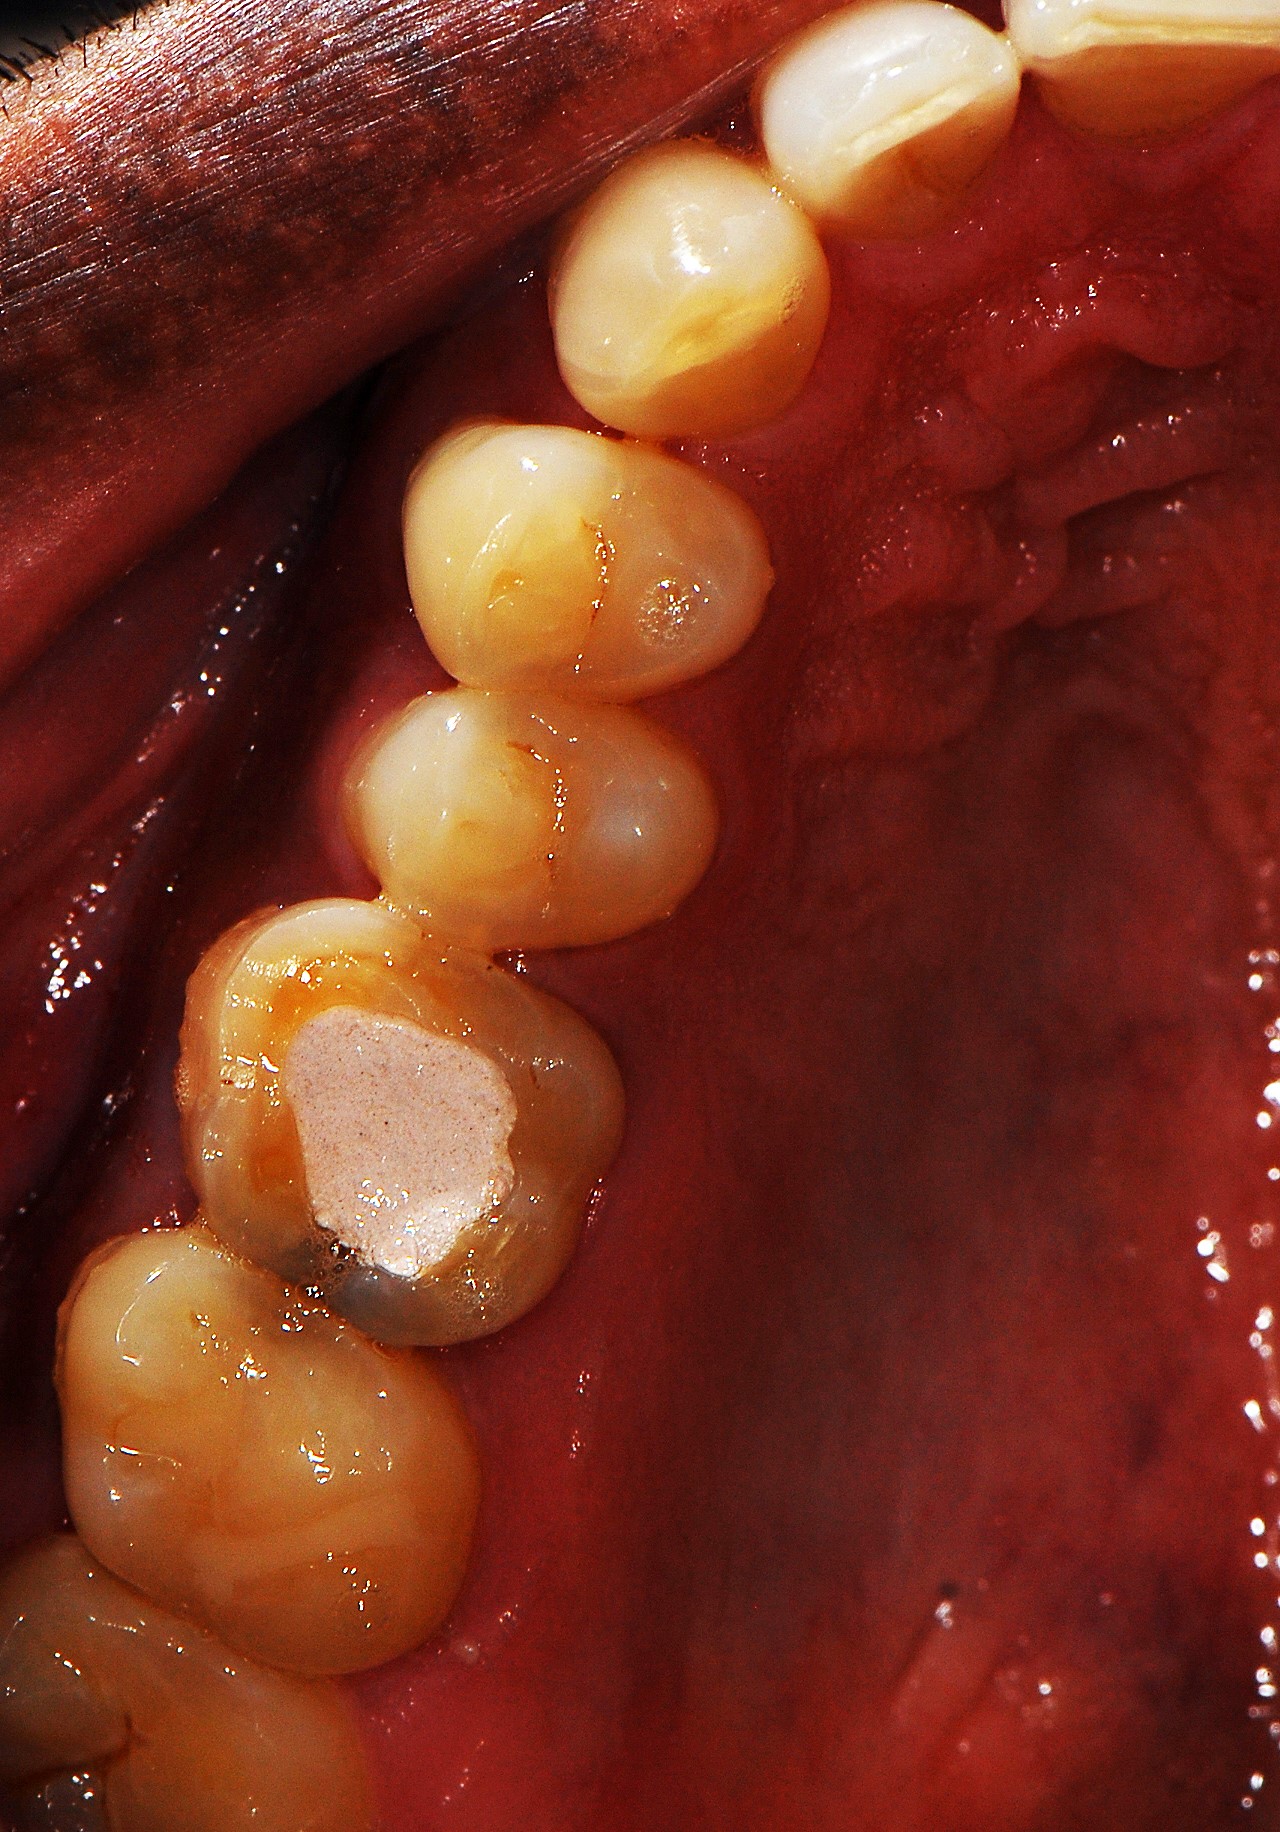

Cementation of Zirconia crowns

Cementation of Zirconia crowns Cementing Zirconia Crowns because of its newness, many dentists refrain from using zirconia crowns or learning how to properly cement them. how to cement zirconia crowns. Try in the restorations, adjust the. Bruxzir zirconia crowns support multiple cementation methods, with either luting or bonding. improvements in zirconia materials and the advancement of digital technology, scanners, and cad/cam. the most. Cementing Zirconia Crowns.